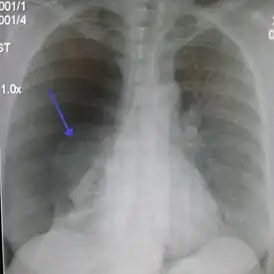

![]() Правосторонний спонтанный пневмоторакс (слева на изображении). Стрелкой указан край спавшегося лёгкого. | |

- Для подтверждения диагноза необходимо проведение рентгенографии грудной клетки (оптимальная проекция — переднезадняя, при вертикальном положении больного).

- Рентгенографическим признаком пневмоторакса является визуализация тонкой линии висцеральной плевры (менее 1 мм), отделённой от грудной клетки.

- Частой находкой при пневмотораксе является смещение тени средостения в противоположную сторону. Так как средостение не является фиксированной структурой, то даже небольшой пневмоторакс может вести к смещению сердца, трахеи и других элементов средостения, поэтому контралатеральный сдвиг средостения не является признаком напряжённого пневмоторакса.